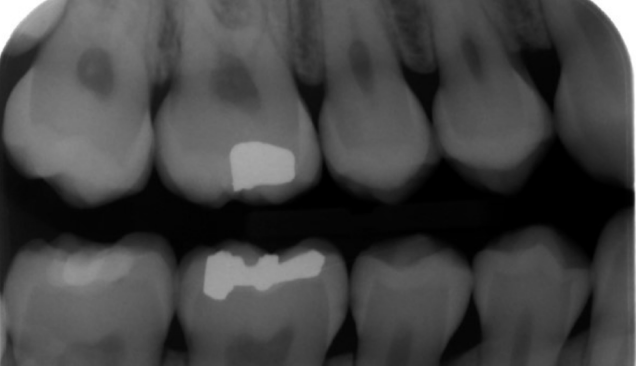

radiographic report

A

Restorations occlusal 16 and 46 amalgams, 47 (composite)

Interproximal caries possible 45 and 46

45 likely just into dentine distal xrays 6 months behind

White shadow in 17 - pulp stones - calcifications - asymptomatic